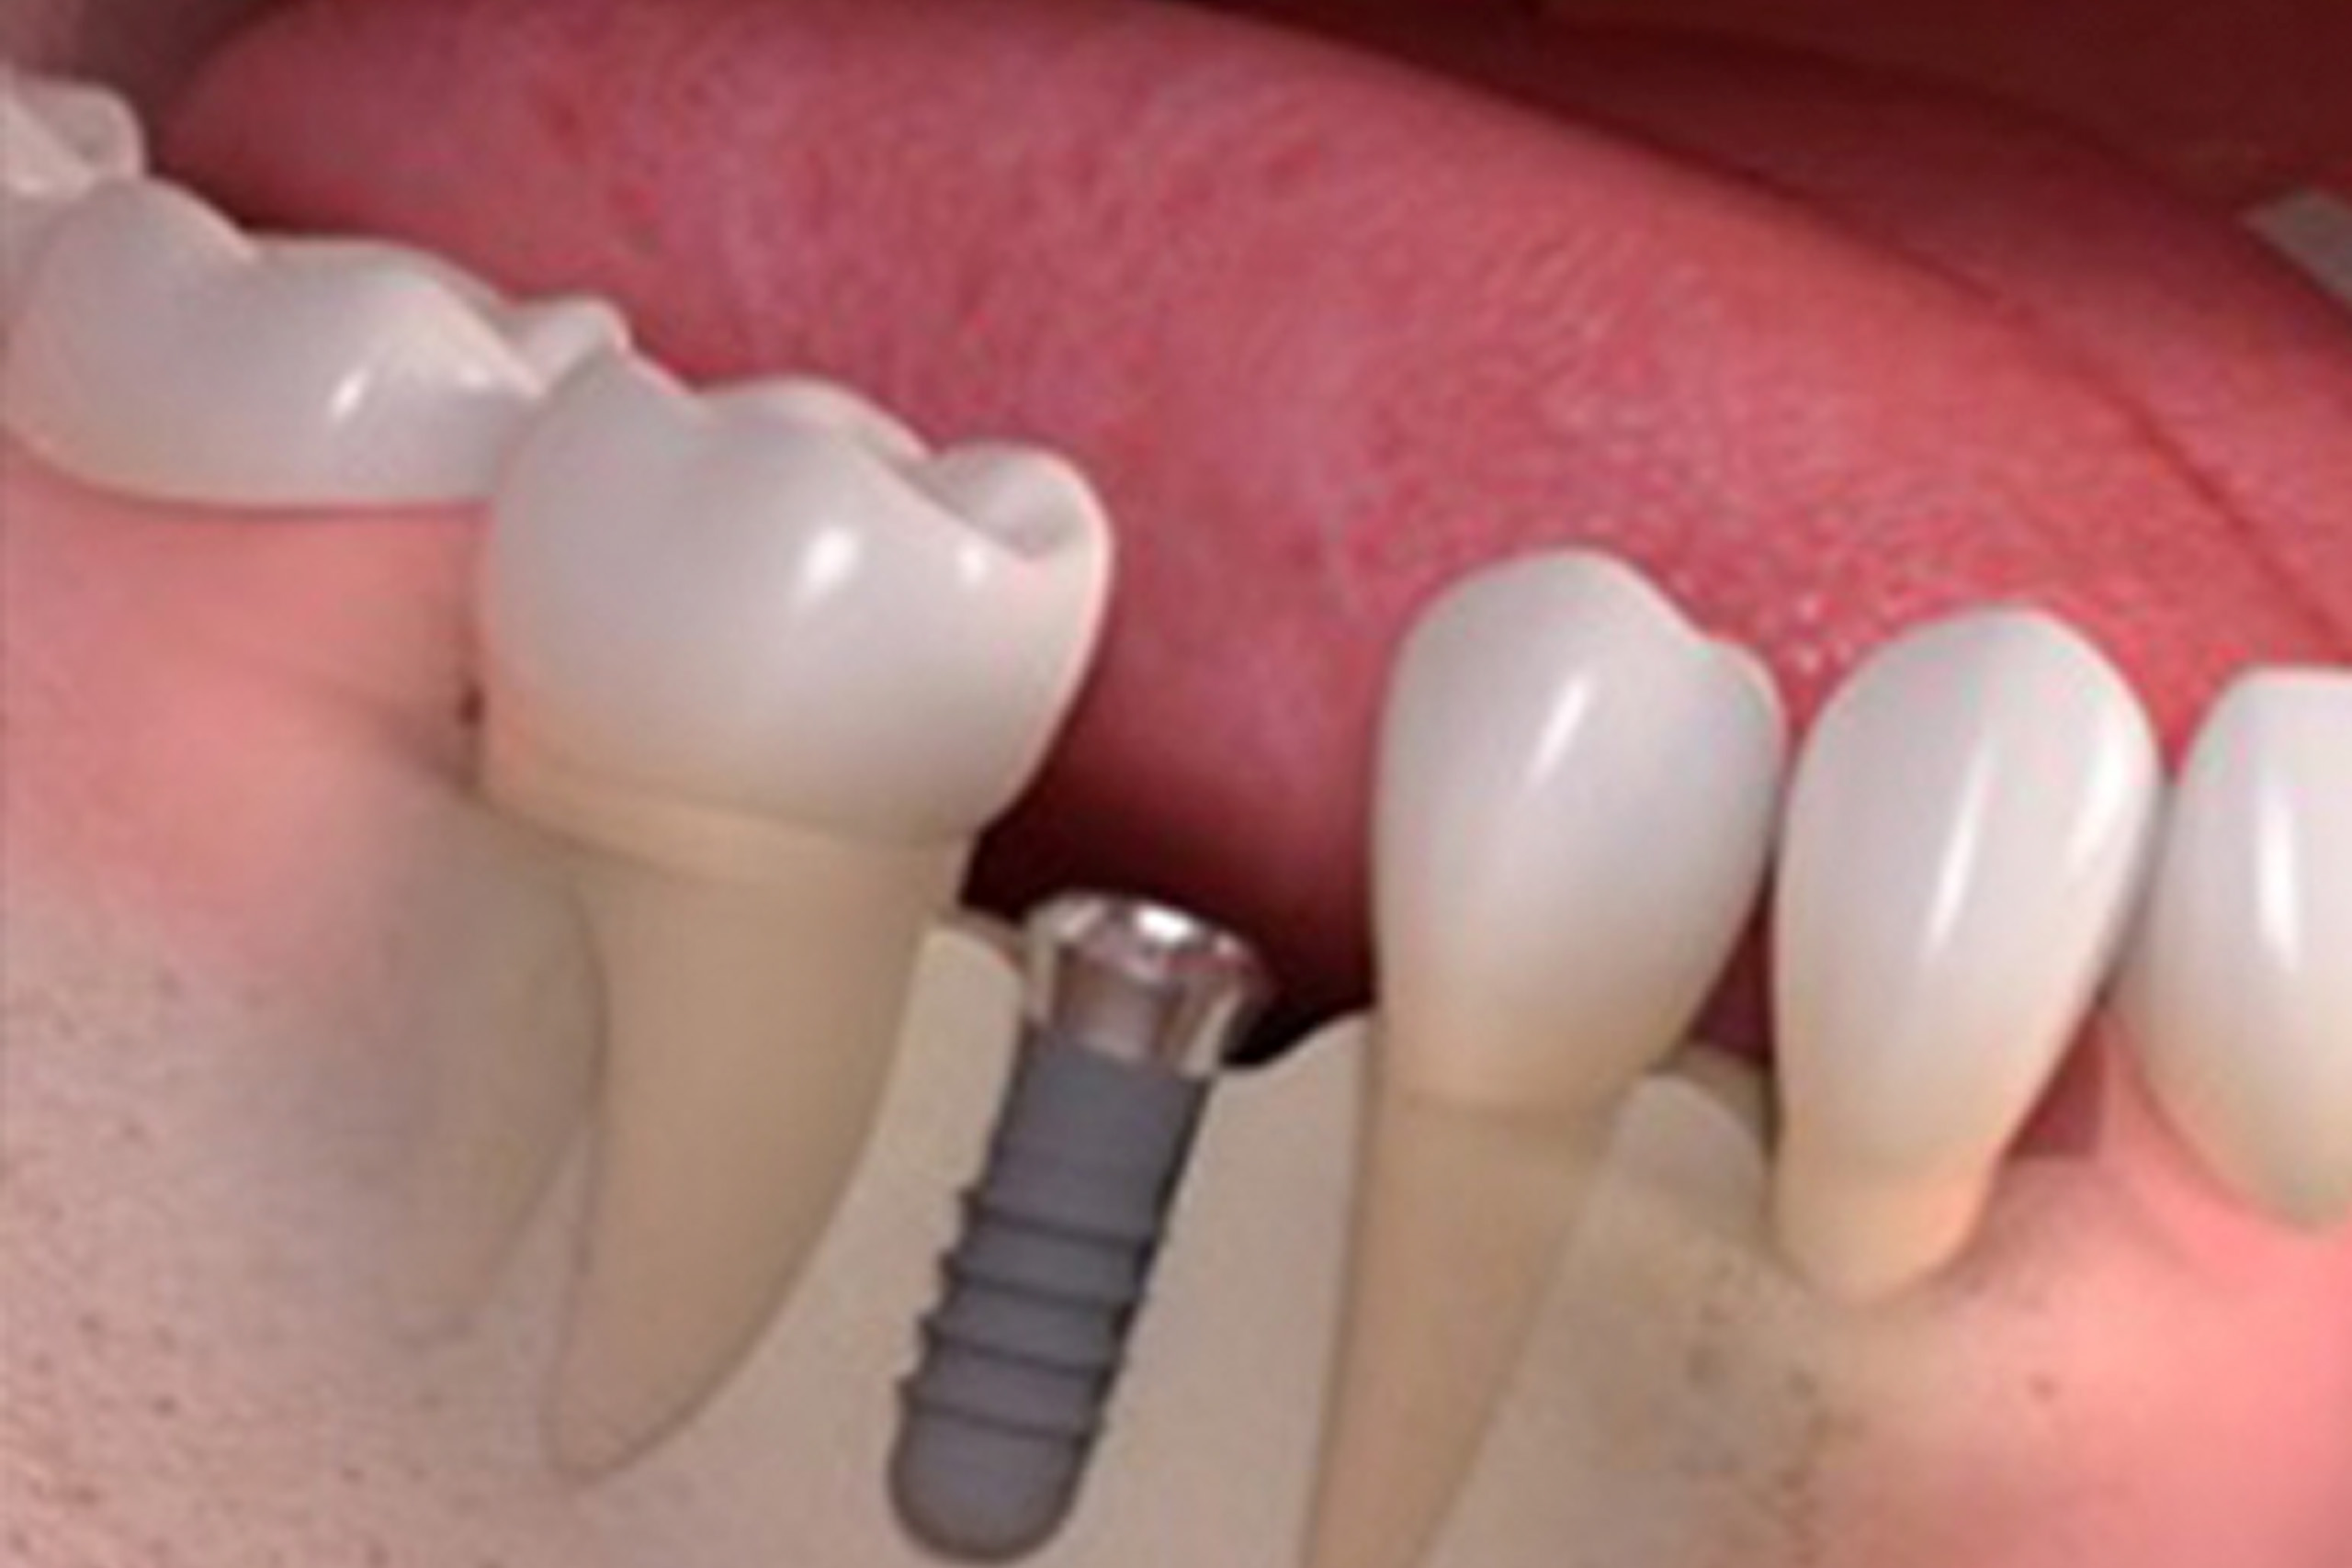

【BLT(ボーンレベルテーパード) 】

やわらかい骨などに使用難症例など幅広く対応できる前歯など見た目重視の部位に最適

BLT(ボーンレベルテーパード)